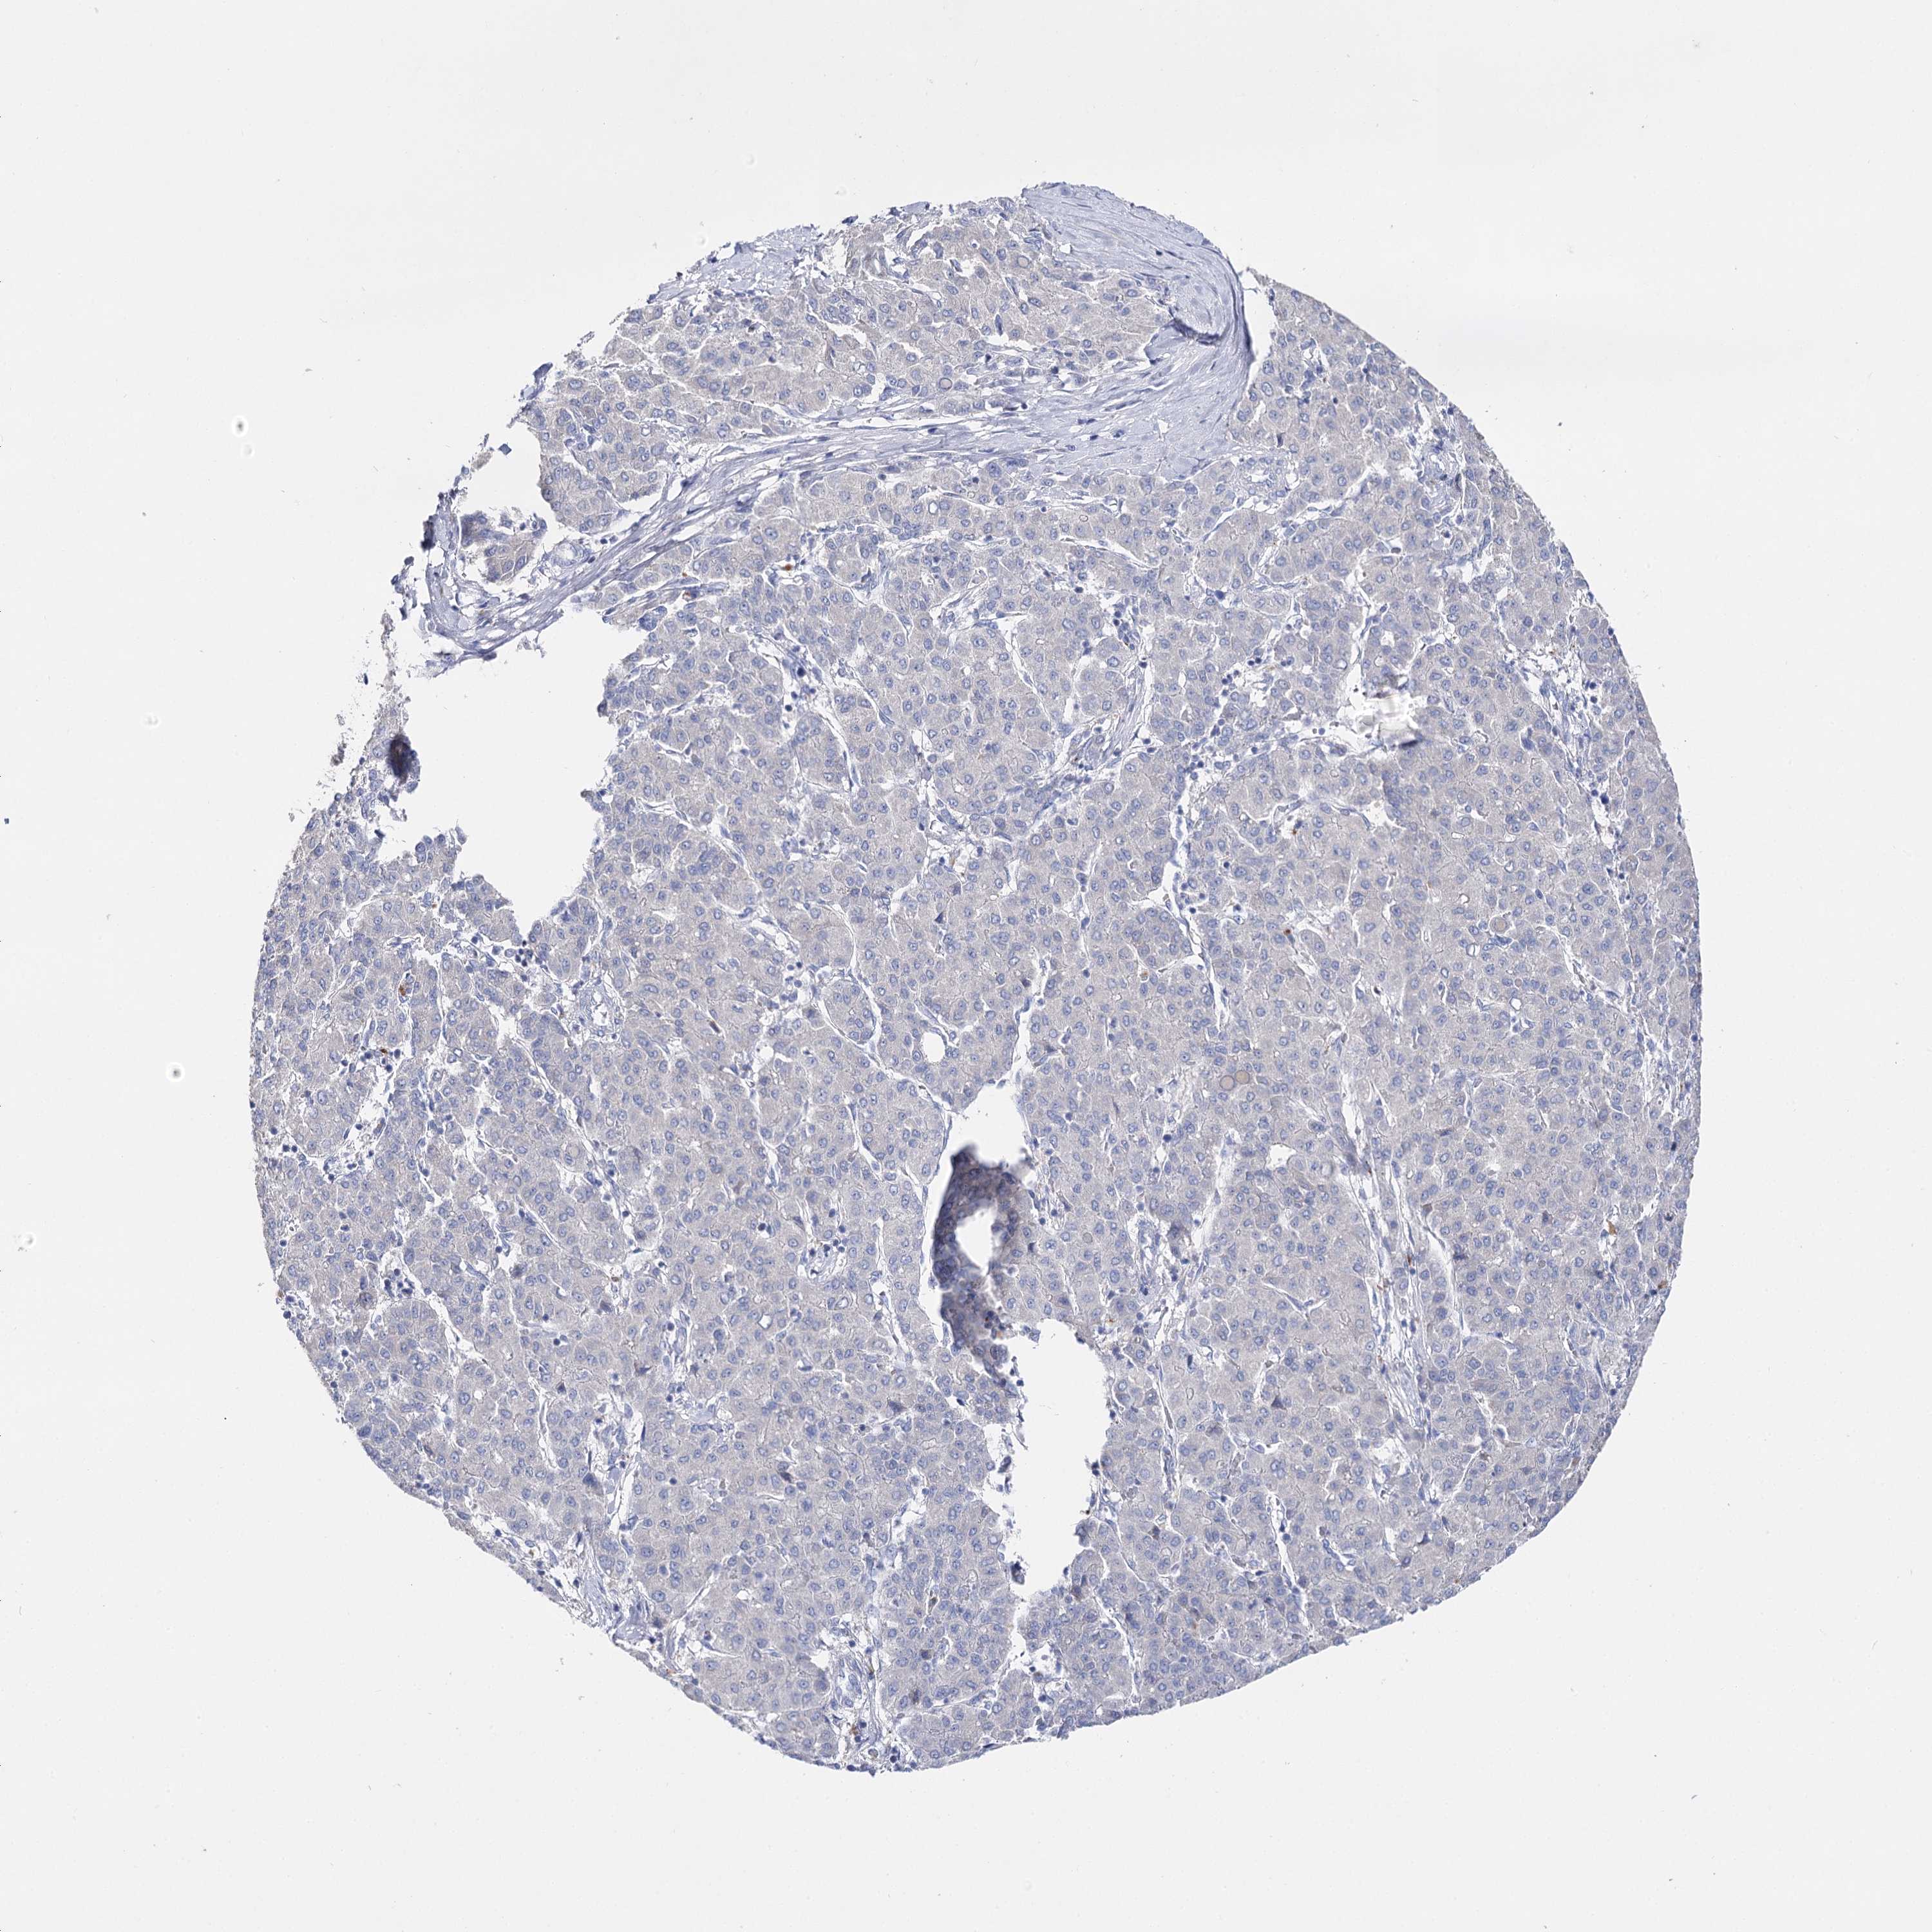

LIVER CANCER - Protein expressioni

A mouse-over function shows sample information and annotation data. Click on an image to view it in a full screen mode. Samples can be filtered based on level of antibody staining by selecting one or several of the following categories: high, medium, low and not detected. The assay and annotation is described here.

Note that samples used for immunohistochemistry by the Human Protein Atlas do not correspond to samples in the TCGA dataset.

Antibody stainingi

Antibody staining in the annotated cell types in the current human tissue is reported as not detected, low, medium, or high, based on conventional immunohistochemistry profiling in selected tissues. This score is based on the combination of the staining intensity and fraction of stained cells.

Each image is clickable and will lead to virtual microscopy that enables deeper exploration of all samples and also displays staining intensity scores, fraction scores and subcellular localization as well as patient and tissue information for each sample.

Antibody HPA037953

Antibody HPA037954

Staining

High

Medium

Low

Not detected

Intensity

Strong

Moderate

Weak

Negative

Quantity

>75%

75%-25%

<25%

None

Location

Nuclear

Cytoplasmic/membranous

Cytoplasmic/membranous,nuclear

Cholangiocarcinoma

Carcinoma, Hepatocellular, NOS